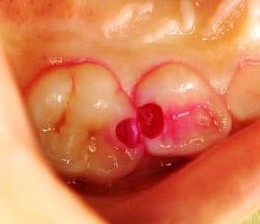

小さな子供の歯は大人の歯よりも小さいため、「削りすぎない」ことや、「経過観察」が重要です。当院では、お子さんの歯を過剰に削らないよう、以下の取り組みを行っています。

健康な歯を不必要に削るリスクを軽減するため、う蝕検知液を使用します。虫歯になった部分だけを赤く染める薬剤です。